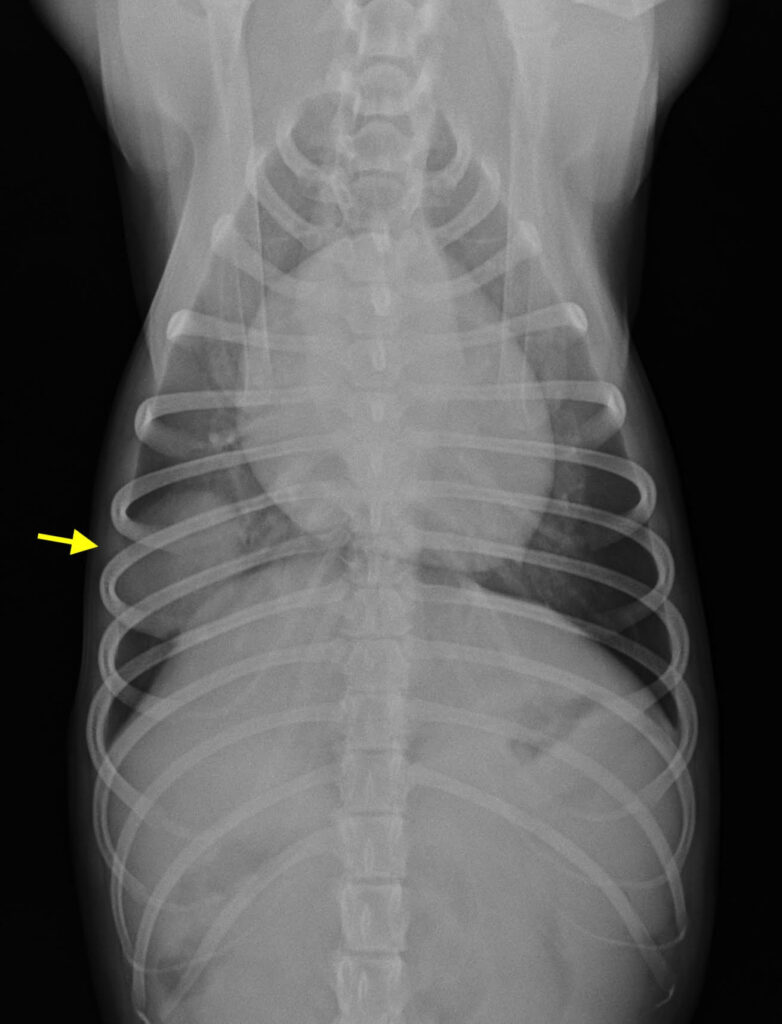

この症例は無症状でしたが、健康診断のレントゲン検査で、肺に単発性の腫瘍が発見されました。

腫瘍の発生部位や転移の有無を精査するため、他院でCT検査を行なってもらい、外科的切除が適応と判断しました。